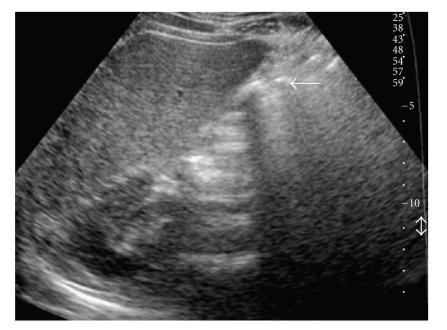

Gallbladder agenesis (GA) is a rare congenital anomaly of the biliary system often associated with other congenital abnormalities. Patients become symptomatic in 23% of cases. GA is often misinterpreted as other diseases, therefore, leading to unnecessary surgery. We report a case of congenital GA associated to cystic duct absence and a biliary tract abnormality diagnosed by Magnetic Resonance with Cholangiopancreatography.

胆囊缺如(GA)是一种罕见的胆道系统先天性异常,常与其他先天性畸形相关。23%的病例会出现症状。GA常被误诊为其他疾病,因此导致不必要的手术。我们报告一例先天性GA合并胆囊管缺如及胆道异常的病例,该病例通过磁共振胰胆管造影诊断。